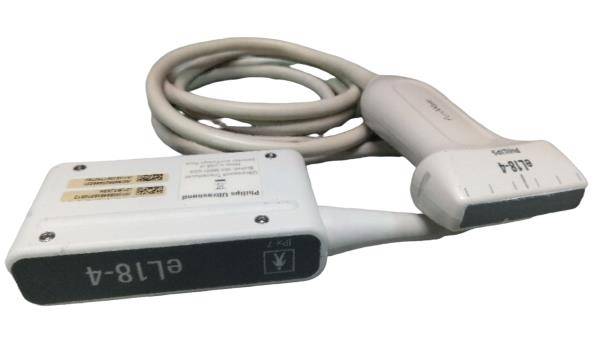

DIAGNOSTIC ULTRASOUND MACHINES FOR SALE

Ultrasund Probe Transducer TOSHIBA PST-65AT

Sale price$ 3,344.48